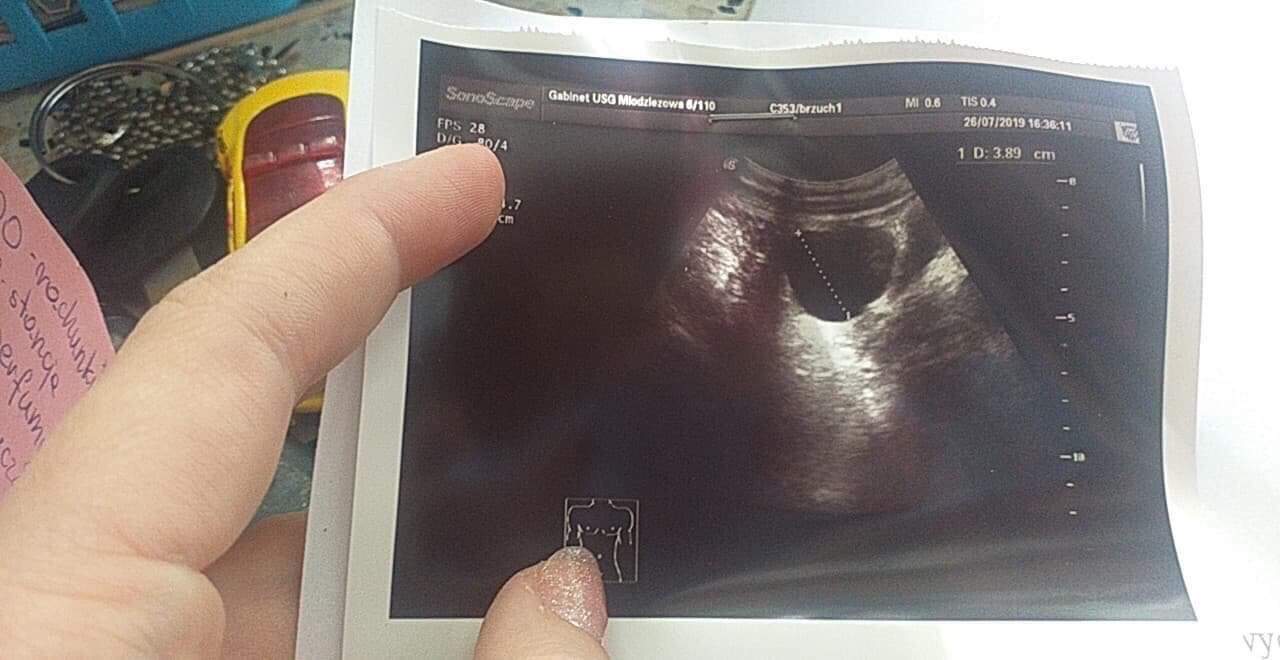

Hejka dziewczyny, mój kolega dostał od byłej dziewczyny zdjęcie usg, chcemy się upewnić czy go nie wkreca, pomożecie? Zdjęcie dodaje w załączniku

Nie ma tam zarodka, ciąży nie widać. Wklejam Ci dla porównania moje zdjęcie ciąży 7 tydzień. Wyraźnie widać pęcherzyk ciążowy, ciałko żółte i zarodek (ta kropeczka w środku to cewka serca).